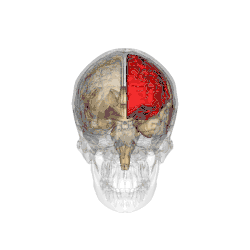

Functional magnetic resonance imaging (fMRI) scans of the brains of subjects exposed to thirty-five hours of sleep deprivation indicate that sleep deprivation is related to increases in prefrontal cortex and parietal lobe activation during tasks that combine verbal learning and arithmetic. This is particularly apparent in the right hemisphere. In non-sleep-deprived people involved in verbal learning and arithmetic tasks, the anterior cingulate cortex and the right prefrontal cortex are active. Following sleep deprivation, there is increased activation of the left inferior frontal gyrus and the bilateral parietal lobes. This information suggests that divided attention tasks require more attentional resources than normally required by a non-sleep-deprived person.[5]

Deficits in cognitive performance due to continuous sleep restriction are not well understood. Studies have looked into physiological arousal of the sleep-deprived brain. Participants, whose total amount of sleep had been restricted by 33% throughout one week, were subjected to reaction time tests. The results of these tests were analyzed using quantitative EEG analysis. The results indicate that the frontal regions of the brain are first to be affected, whereas the parietal regions remain active until the effects of sleep deprivation become more severe, which occurred near the end of the week. EEG and ERP analysis reveals that activation deficits are more apparent in the non-dominant hemisphere—than in the dominant hemisphere.[11]

By contrast, other studies have indicated that the effects of sleep deprivation on cognitive performance, specifically sustained visual attention, are more global and bilateral in nature (as opposed to more lateralized deficit explanations). In a study using the Choice Visual Perception Task, subjects were exposed to stimuli appearing in various locations in visual space. Results indicate that sleep deprivation results in a general decline in visual attention. It is also suggested that the sleep-deprived brain is able to maintain a certain level of cognitive performance during tasks requiring divided attention—by recruiting additional cortical regions that are not normally used for such tasks.[14]

The parietal lobes of the brain are largely involved in attention. Lesions to this region of the brain in humans result in difficulty or inability to attend to events that are contralateral to the lesioned hemisphere. Those with lesions to the posterior parietal lobe have little to no difficulty shifting attention to and from stimuli appearing in the space ipsilateral to the lesioned hemisphere. They display a slowed response in shifting their focus of current attention to events and stimuli appearing contralateral to the lesioned hemisphere.[15]